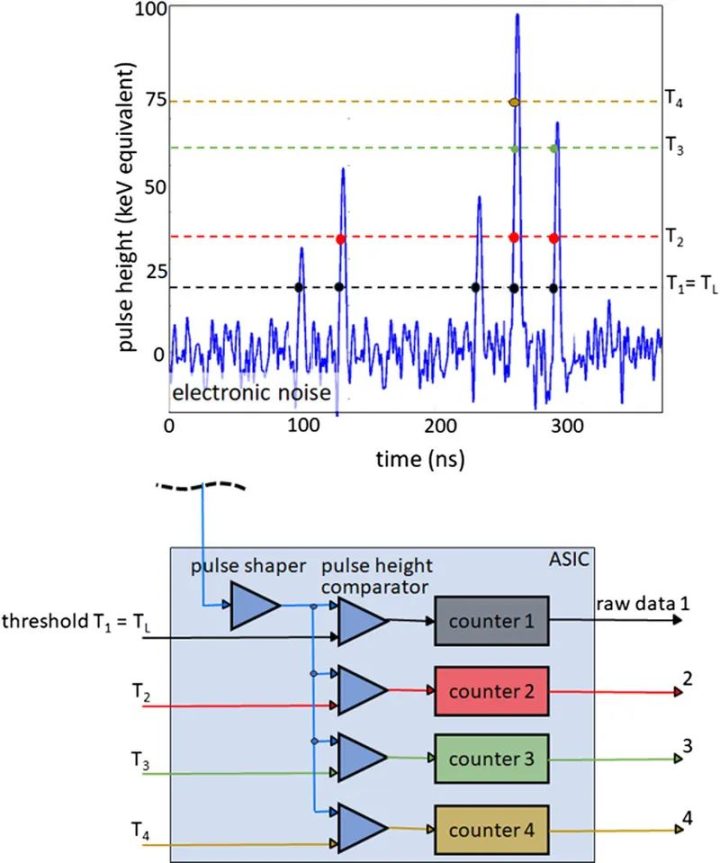

为了获得光谱分辨数据,需要同时读出在不同阈值能量下工作的多个计数器,见图2。然后,探测器为每个阈值提供单独的数据流,其中只包含能量超过相应阈值能量的X射线量子,另见图2。从包含能量超过最低阈值能量TL的所有X射线量子的数据流中重建的图像(TL图像,西门子公司专有,也称为T3D图像)可与传统CT在相同的X射线管电压(kVp)下获得的图像相媲美。然而,在现实的PCD中,由于不可避免的物理效应降低了信号的光谱分离度,如像素边界的电荷共享或荧光导致的X射线量子能量损失,能量登记存在误差。这些效应的示意图如图3所示,它们会导致量子在X射线能量过低时被错误地计数两次。与CdTe-PCD或CZT-PCD相比,硅PCD受电荷共享和荧光的影响较小,因此光谱分离效果较好,但大多数X射线量子主要在硅晶体中散射,而不是直接吸收;它们经常离开探测器像素而不产生信号,因此探测器的探测量子效率降低,所有探测任务都需要更高的辐射剂量。在非常高的X射线通量下,产生的电压脉冲在时间上重叠,不再单独计数。然而,在实际的CT通量率下,脉冲堆积并不起作用。

图2 使用PCD采集光谱数据的示意图。上图所示为吸收不同能量的X射线量子所产生的电压脉冲时间序列。下图是一个4门限计数器的技术实现示意图。在此示例中,同时读出4个计数器的阈值能量分别为20、35、60和75 keV。探测器提供4个原始数据流,其中只包含吸收能量大于各自阈值能量的计数X射线量子。